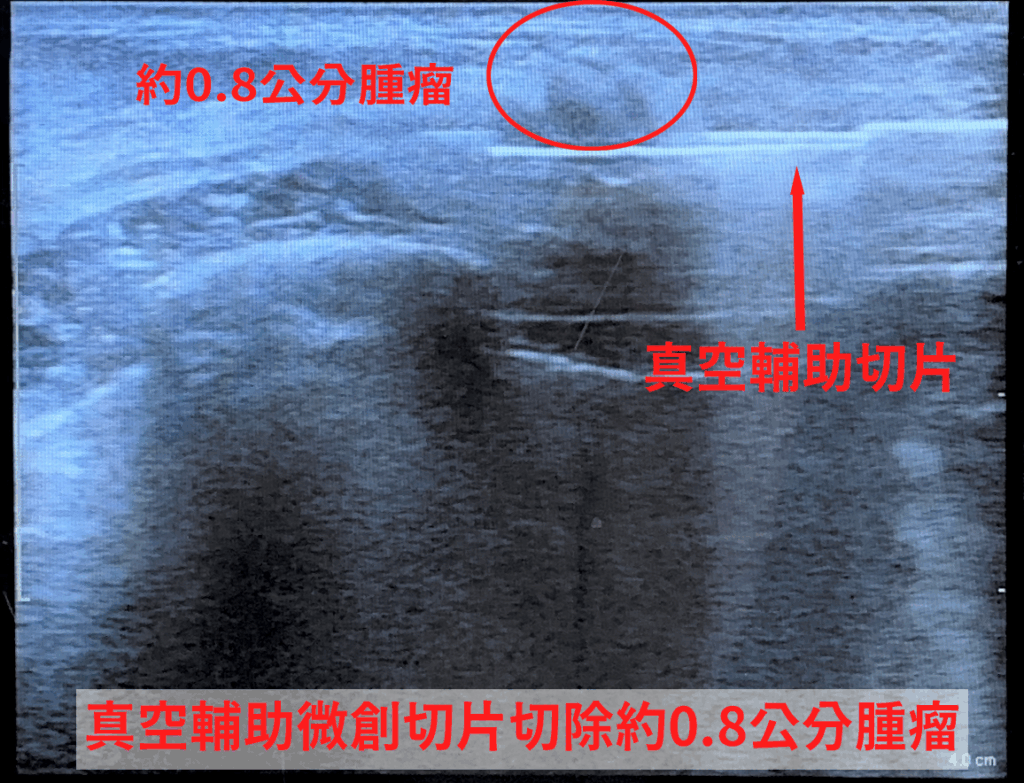

一名年僅24歲的年輕女性,近日因乳房疼痛就醫,求診中國醫藥大學新竹附設醫院乳房外科主任古君平,透過超音波檢查發現約0.8公分不規則邊緣腫瘤,且伴隨微鈣化。雖然初次以傳統粗針切片檢查結果為良性,但影像仍顯示有異常,醫師認為癌症的風險大概10%甚至50%,醫病溝通後,進一步以「真空輔助微創切片」取得更多組織,提升診斷準確度,也可同步完整移除腫瘤。

以真空輔助微創手術,切開的傷口藏在乳房側面,或是在乳暈的邊緣,傷口大概0.3到0.5公分,比傳統的傷口小非常多,而且透過微創的切割,可以精準在超音波下判斷腫瘤位置,保留周邊乳腺組織,乳房外觀幾乎不受影響,乳房乳腺乳暈的破壞也比較少一點。手術時間約半小時即可完成,相比傳統2至3公分切口的手術,傷口更小、破壞更少,術後恢復快。